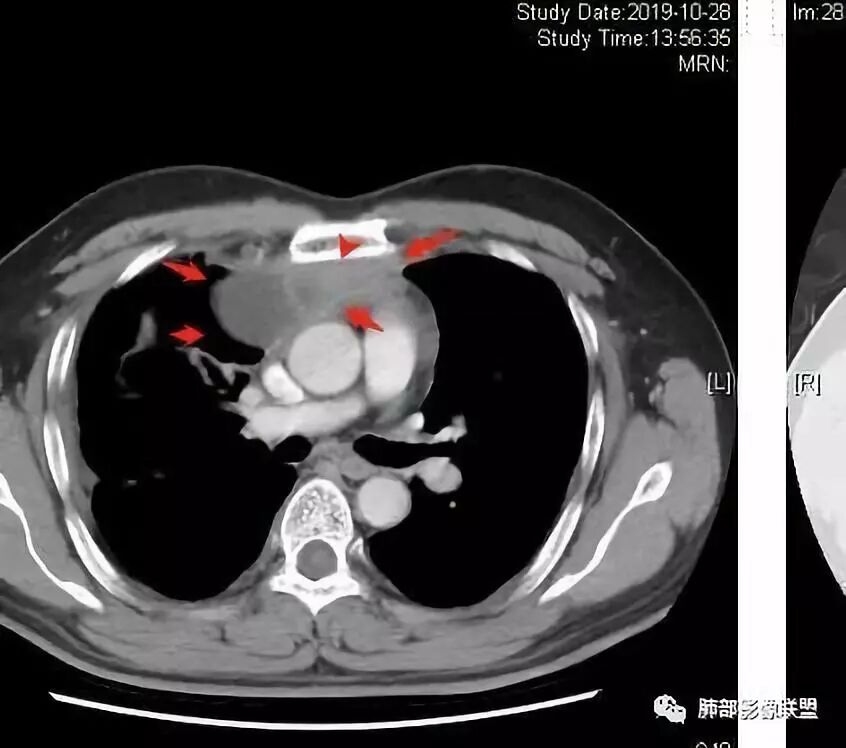

穿越七海的风:右前纵隔占位,恶性肿瘤,生殖来源?右肺实变是占位or肺不张?考虑为部分肺不张FeNo:右前纵隔占位,右肺结节,胸膜凹陷,小尾巴,右肺不张,考虑恶性杨旭华:恶性,前纵隔肿物,与血管关系密切,上腔静脉变窄,右肺野一元论考虑叶间裂增厚,恶性胸膜间皮瘤可能大小丽:到底是纵隔来源还是胸膜来源?我怎么倾向于胸膜来源,和叶间胸膜关系密切,而且纵隔内上腔静脉是向内侧推移。胸膜肿瘤(间皮瘤?SFT?)包裹性胸腔积液?马春平(张家港市一院胸外科):前纵隔占位,左无名受压,右大量胸腔积液可能是胸导管汇入处侵犯受压,考虑纵隔鳞癌孙冰伟:右上纵隔占位,也感觉和叶间胸膜关系密切,右侧胸膜局限性增厚,考虑恶性可能性大灵:前纵隔占位,血性胸水,胸膜凹凸不平,查见肿瘤细胞,结合免疫组化考虑胸腺癌。鉴别胸膜间皮瘤。采莲:右前上纵膈旁可见类圆形肿块,纵隔血管内移,感觉来源于胸膜,肿块内密度低,似水样密度,右侧胸膜广泛增厚,少量胸腔积液。心包少量积液。考虑胸膜间皮瘤,鉴别肺癌并胸膜转移?水晶石头:患者中年男性,胸闷15天。有“高血压、慢性肾小球肾炎”病史。查肿瘤标志物正常,胸水提示渗出液,胸水病理查见瘤细胞。胸部CT:右肺上叶后段结节、斑片影,见胸膜牵拉、包裹积液及部分纤维条索灶,似见卫星灶,右侧胸膜增厚。前纵隔脂肪密度增厚,右侧可见类圆形低密度(液体)肿块,边缘光滑。综合考虑右肺腺癌并胸膜转移,结核可能。周太狼:考虑纵隔胸膜来源肿瘤,恶性,胸膜间皮瘤伴转移?徐飞:中年男性,影像为右侧胸腔及叶间积液,叶间胸膜增厚轻度强化。前纵隔右侧心缘旁团块,可见坏死。胸水见癌细胞,综合考虑恶性,胸腺癌伴转移。小赵:中年男性,血性胸水,常规查见癌细胞,李凡他实验阳性。胸部CT示前纵隔见不均匀密度影,与邻近大血管分界不清,囊变坏死明显,增强扫描呈不均匀强化,心包及右侧胸膜增厚,并心包及右侧胸腔少量积液。综合考虑胸腺癌。右肺中叶病变周围见多发纤维条索,支气管部分进入病灶,考虑炎性病变。流心明智:患者,男性,50岁。胸闷15天。高血压20年,慢性肾小球肾炎15年。肿标正常,胸水提示渗出液,胸水查见癌细胞。胸部CT:右肺肿块影,斑片影,索条影,可见胸膜牵拉、多发包裹积液,纵隔上腔静脉受累,心包受累。综合考虑:ROSE似腺?考虑右肺腺癌并胸膜转移,心包受累。鉴别胸腺Ca、淋巴瘤,纵隔病变不懂,等老师们精彩分析。王秀仙:前纵膈囊实性肿块,与纵膈分界不清,心脏大血管及上腔静脉受压向内后移,右侧后胸膜、侧胸膜增厚,右侧叶间裂不规则增厚,心包积液,根据腔静脉移位情况,考虑纵膈胸膜来源恶性肿瘤,胸膜间皮瘤?鉴别胸腺癌并胸膜转移。高广飞:上纵隔占位,右侧叶间胸腔积液,需考虑恶性自信人生:多发囊实性病灶,包裹性积液,考虑胸膜来源 只是没有看到壁结节,恶性胸膜间皮瘤巴伟:前上纵隔占位,胸膜及心包结节,考虑胸腺瘤或癌,右肺病灶,先考虑陈旧炎性病变。Lenle董:前纵隔占位,部分边缘模糊,病灶内囊变?坏死?上腔静脉受侵,考虑胸腺癌;叶间片状影,强化明显,炎性考虑。常志强:前纵隔囊实混杂密度肿块,边界不清,实性部分强化明显,结合胸水内见癌细胞,考虑恶性肿瘤伴转移。飞鹰行动:前纵隔占位,软组织密度及囊性密度,实性部分密度均匀,致密,病灶与周围血管分界不清,增强后病灶强化有类似不温不火强化,部分血管受侵犯,右肺见肿块样病变及条索状病变,一元论,考虑淋巴瘤,二元论,考虑胸腺瘤B2—B3伴右肺病变。尽量一元论考虑,淋巴瘤可能。看图说话:右肺索条病灶,边缘膨隆,胸膜牵拉,考虑右肺癌伴胸膜转移。晨:前纵隔囊实性肿块,与纵隔分界不清,右侧后胸膜、侧胸膜增厚,右侧叶间裂不规则增厚,考虑纵隔胸膜来源恶性肿瘤,考虑胸腺癌并胸膜转移。丽:中年男性,前纵隔囊实性肿块,呈偏心性生长,临近大血管受压推移,增强后实性部分不均匀强化,心包可见条形积液,考虑胸膜来源恶性肿瘤,胸腺癌可能大。另右肺多发斑片状高密度影及实变密度影,实变影呈均匀强化,右侧胸膜局限性增厚,考虑炎性病变。小飞:右前纵隔囊实性占位,实性部分明显强化,右侧叶间胸膜增厚,右侧胸腔积液,心包积液,考虑恶性胸腺瘤!尘缘:支持恶性胸腺瘤(囊实性肿块,实性强化,且侵犯纵隔,脂肪间隙模糊)伴肺内及胸膜转移。浪迹天涯:考虑侵袭性胸腺瘤——胸腺前纵隔占位,周围脂肪间隙模糊不清。尘缘:不除外另一种可能:二元,肺内腺癌合并胸膜转移,纵隔的畸胎瘤可能。一米阳光:晨读中年男性,右肺结节影,叶间裂及胸膜增厚牵拉,右侧胸水。心包多发结节改变。胸水查见癌细胞。考虑,腺癌并转移。鉴别,胸膜间皮瘤并转移前纵隔囊实性占位,二元考虑。心灵鸡汤:老年男性,右肺中叶外段长条状软组织密度影,边缘膨隆,邻近胸膜牵拉,部分胸膜有栽脏,右中叶外侧段支气管堵塞,常规考虑恶性肿瘤,腺癌可能,结核、鳞癌不除外,另右肺上叶斑片影,小叶性肺不张?右前纵隔囊实性不规则形密度影,其内见部分脂肪样极低密度影,与邻近血管边界不清,心包外膜有侵犯,增强未见纵隔窗平扫,实性及分隔见增化,其内低密度影未强化,考虑低度恶性纵隔肿瘤,间皮瘤可能,畸胎瘤、淋巴瘤待排,建议支气管镜及穿刺活检。曹志勇:右前纵隔考虑来源于胸膜的恶性肿瘤,右肺内病灶考虑鳞癌,二元德芙~云味:中年男性,右肺见结节、斑片影,右侧包裹积液、胸膜牵拉,纤维条索,前纵隔囊性占位,考虑腺癌、并转移。欧阳英:右前中纵隔囊实性肿块及右肺内结节灶,支持恶性肿瘤,胸腺癌并肺内转移可能张延军:前纵隔见不规则软组织影,密度不均,右侧缘见囊变区,纵膈及侧胸壁胸膜增厚,增强呈不均匀强化,右肺中叶见结节灶,近段支气管阻塞,叶间胸膜不规则增厚,考虑1:右肺中叶腺癌伴纵膈及胸膜转移;2:前纵膈侵袭性胸腺瘤并胸膜侵犯,中叶炎性改变?彭君:老年,前纵隔占位 ,坏死边缘清, 侵犯心包 右侧胸膜及叶间胸膜结节 ,少量胸水, cea不高 ,考虑恶性, 间皮瘤可能 ,转移待除外。毛勤香:恶性没问题,胸水查见癌细胞,一元还是2元,右肺中叶肿块,边缘毛糙,局部似有毛刺,周围有粘连,右侧胸膜腔少量积液,胸膜增厚多发结节,含叶间裂结节,纵膈脂肪间隙模糊,纵膈胸膜增厚,心包增厚积液,右前那个类圆形低密度肿块,纵膈血管内移,我考虑胸膜来源可能性大,综合考虑,一元肺腺癌并多发转移,二元考虑胸膜间皮瘤并多发转移,肺内炎症不张。

南边:大家看看前纵隔的病灶,符合肿瘤吗脂肪,周围密度增高

三个石头:比较散;像炎症的蔓延生长南边:是,这些看着心里不踏实觉得把这个纳入肿瘤去考虑是否合适总觉得边缘收缩的、散在的朝周围蔓延;中央还跨过脂肪,朝对侧胸膜蔓延把这个与囊性病变连到一起去考虑是否还需要斟酌一下因为这个就方向差异大了南边:连在一起,囊实性,边界不清,自然考虑恶性:如果独立,囊张力高、边界清楚,间隔,自然朝良性考虑:

Coke with ice:囊性部分考虑包裹性积液?南边:不是积液;有间隔;张力高;而且位置有些特殊

大家仔细看看积液中的游离气体;

不是支气管,是积气;是穿刺进去的;

囊内密度不一致

我认为囊张力高,积液中的气体均在周围,外侧、下方,囊内有间隔:各腔密度不一致;提示:囊腔属于前纵隔,不是包裹性积液;现在的问题:囊腔与内侧的病灶是否是一体的

南边:我总觉得这个纵隔内不像是一个肿块的改变,扁平,周围蔓延:有符合炎性的的特点,或者肿瘤的侵犯;但是肿瘤的侵犯,不大符合,实性部位的边缘过于柔和,没有毛糙的侵犯边缘。

南边:纵隔囊性病变:良性?恶性:胸腺癌?

2、前纵隔内病灶囊实性混杂密度病灶,囊性病灶主要位于右侧,张力较高,有分隔影,囊壁右侧缘光整,病灶左侧实性部分边界不清明显强化,病灶肺瘤交界面大部分边界清楚,部分模糊。

前纵隔肿块伴囊变坏死常见以有胸腺瘤、胸腺癌、淋巴瘤和生殖细胞肿瘤。

纵隔内病灶不符合肺癌转移途径,且纵隔内单发的囊实性转移罕见。淋巴瘤无论是分布、形态、密度、还是强化方式度不符合。

胸腺瘤/胸腺癌符合吗?

胸腺瘤/胸腺癌:病灶内那么大的囊,常规考虑B型以上胸腺瘤,囊内有分隔影,病灶周围脂肪间隙模糊,常规考虑侵袭性胸腺瘤或胸腺癌,若侵袭性胸腺瘤,常侵犯胸膜、心包,很少累及肺。胸腺癌易侵犯胸膜、肺并纵隔淋巴结及远处转移。但肺内腺癌形态更符合原发灶。胸膜及叶间裂转移则即可来自肺,也可来自胸腺癌。